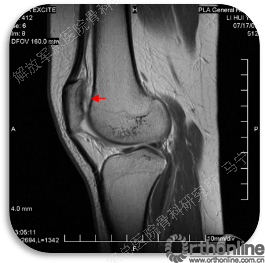

首先经过核磁的检查、评估,初步确定软骨损伤范围,利用T2maping检测序列对软骨的信号区分。图中我们可以看到软骨损伤的范围,并通过计算机计算出大概的面积。

患者,男,26岁,右膝关节间断性疼痛3年,关节屈曲经过40度时有弹响伴疼痛,发现股骨髁局部软骨缺损。损伤的软骨下骨可见明显水肿。